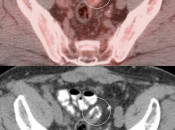

FDG accumulation in tissues generally increases in both normal and malignant tissues for at least 90 minutes before normal washout begins (some studies suggest plateauing of uptake can take up to 3-hours).  Therefore, a patient imaged 45 minutes after injection might demonstrate lower SUV’s than if that same patient had been imaged at 90, 120 or 180 minutes.

This is of particular concern when comparing serial exams.  If the two scans had significantly different time delays before scanning, SUV comparisons may be completely erroneous.  Consequently, following standardized imaging protocols is essential with PET/CT scanning (which may be impossible if the patient was previously scanned at an another facility). [FIG. 3]